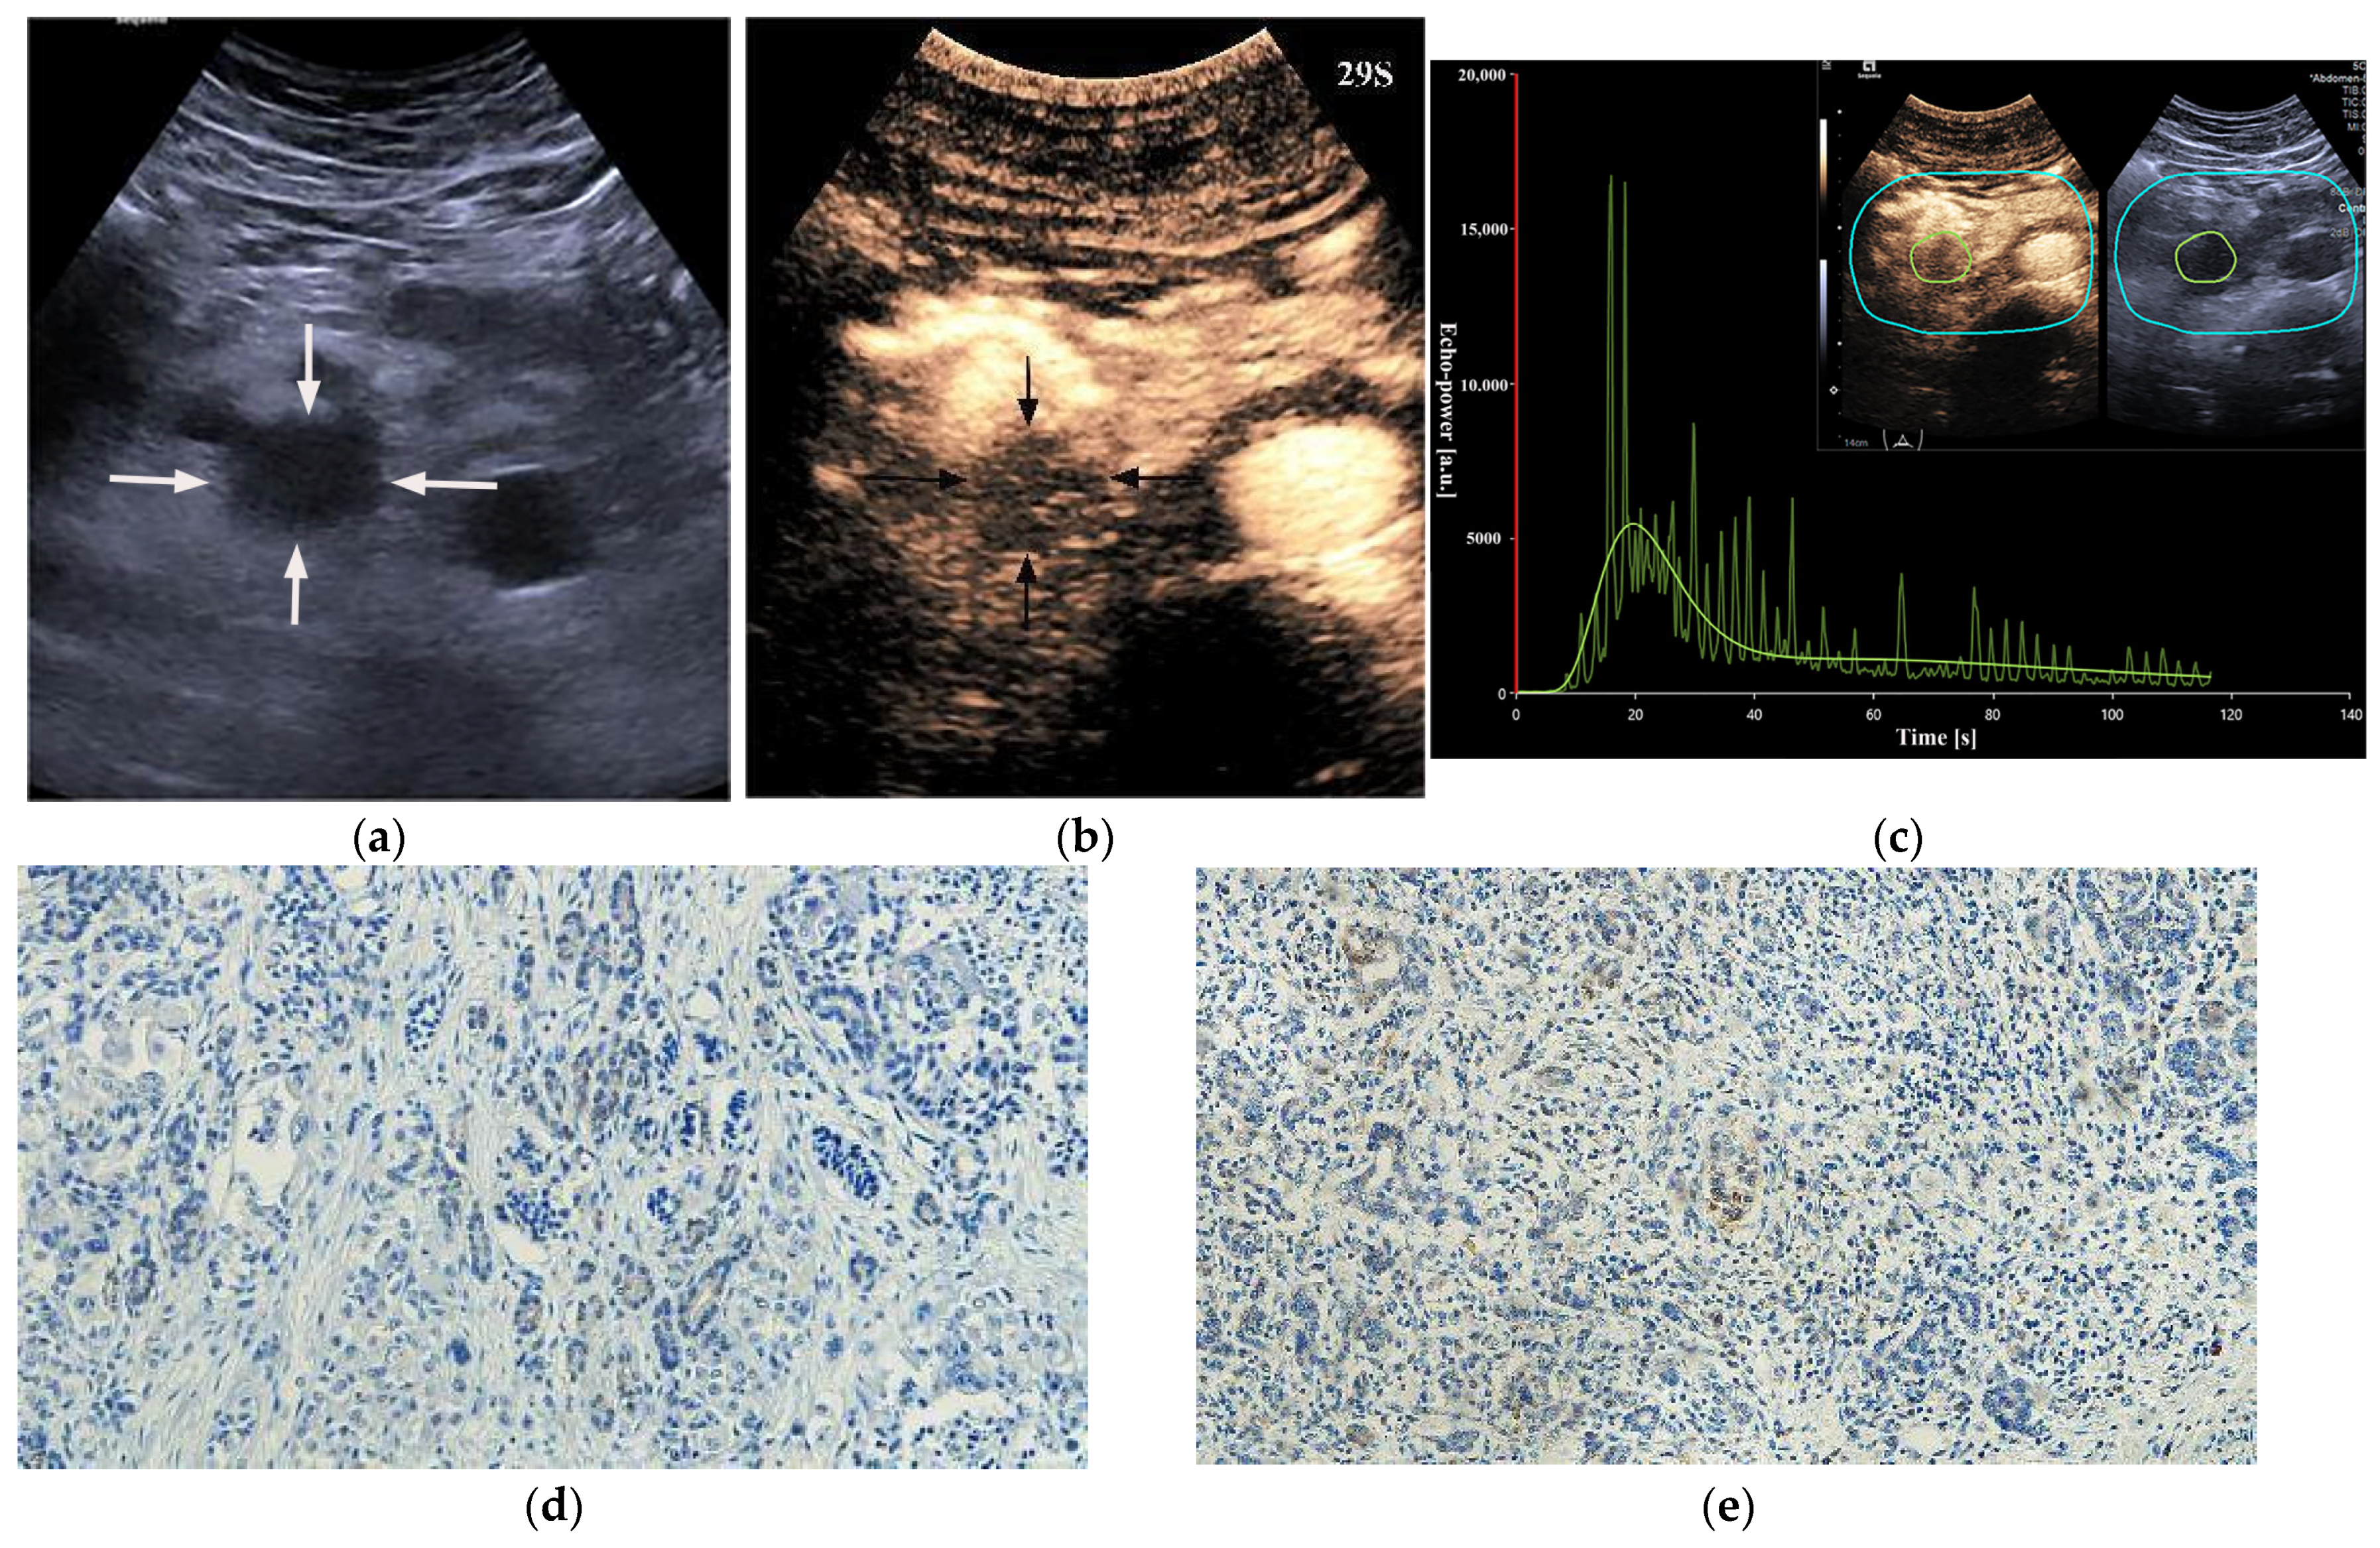

HIF-1α-high PDACs (p = 0.001) and GLUT1-high PDACs (p = 0.003) manifested incomplete enhancement more frequently on CEUS (Figure 2 and Figure 3). In PDACs with ≤50% enhancement, 80% (12/15) showed HIF-1α high expression and GLUT1 high expression. The peak enhancement degree (PED) in HIF-1α-high PDACs (p = 0.027) and GLUT1-high PDACs (p = 0.008) showed iso-enhancement more frequently (Figure 2 and Figure 3) (Table 2).

Figure 3. A 48-year-old male patient with a pancreatic ductal adenocarcinoma. (a) US revealed a hypoechoic lesion (arrows) at the pancreatic tail. (b) The lesion (arrows) demonstrated complete enhancement and hypo-enhancement on CEUS. P = normal pancreatic parenchyma. (c) Photomicrographs of immunohistochemistry stain sections demonstrate a HIF-1α low expression ductal adenocarcinoma (original magnification, ×200). (d) Photomicrographs of immunohistochemistry stain sections demonstrate a GLUT1 low expression ductal adenocarcinoma (original magnification, ×200).